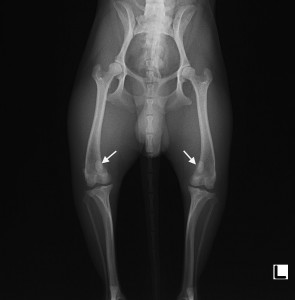

症例は1歳齢のチワワのオス。一週間前より左後肢を引きずっているとのことで来院しました。触診にて両側の膝蓋骨(膝のお皿)が内側へ脱臼していることが分かりました。以下は初診時のX線検査所見です。

矢印で示したように、両側の膝蓋骨が内側へ外れています。股関節や靭帯などの他の部位に異常が無いことを確認し、膝蓋骨内方脱臼による跛行と診断しました。

膝蓋骨内方脱臼がある場合、膝がまっすぐ屈伸できないことで、長い年月をかけて骨が変形し、それに伴い膝の靭帯を損傷する可能性があります。今回、症状が強く現れていたのは左後肢ですが、将来的に骨の変形が進行するのを予防するため、飼い主様と相談の上、両側の膝蓋骨内方脱臼の整復術を行うこととしました。

術後のX線所見です。膝蓋骨が正常な位置へ整復されています(矢印部分)。脛骨(スネの骨)には、変形した骨を骨切りにより矯正し、固定するためにKワイヤーと呼ばれる金属を打ち込んでいます。他、滑車溝(膝のお皿が乗る溝)の造溝や関節包の縫縮など、様々な手技により膝蓋骨を整復しました。